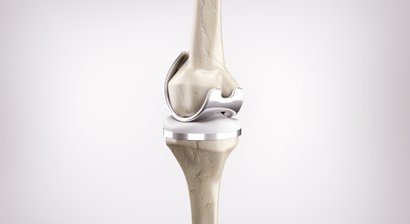

Knieprothese

Eine Knieprothese ersetzt ein verschlissenes Kniegelenk - die Aufgabe der Prothese ist es, die Form und Funktion des menschlichen Kniegelenks nachzuahmen.   Die Implantation von Knieprothesen zählt zu den häufigsten Eingriffen im Bereich der orthopädischen Chirurgie und ist ein wichtiges Spezia...